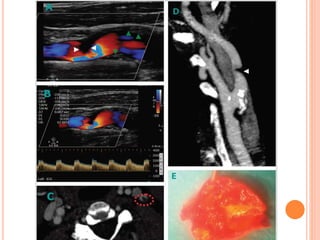

5- ULTRASONOGRAPHY MAY ASSIST IN THE DIAGNOSIS

OF CAROTID OR VERTEBRAL ARTERY DISSECTION.

 Cervical duplex ultrasonography may detect reversed

systolic blood flow at the origin of the vessel and absent

or minimal diastolic blood flow that concurs with high-

resistance bidirectional Doppler signal.

 In B-mode imaging, a tapered lumen with a characteristic

string sign appearance may be shown, as well as a

floating intimal flap. The true lumen can be compressed

by the false lumen thrombus, and subsequently a low-

velocity Doppler waveform can be recorded